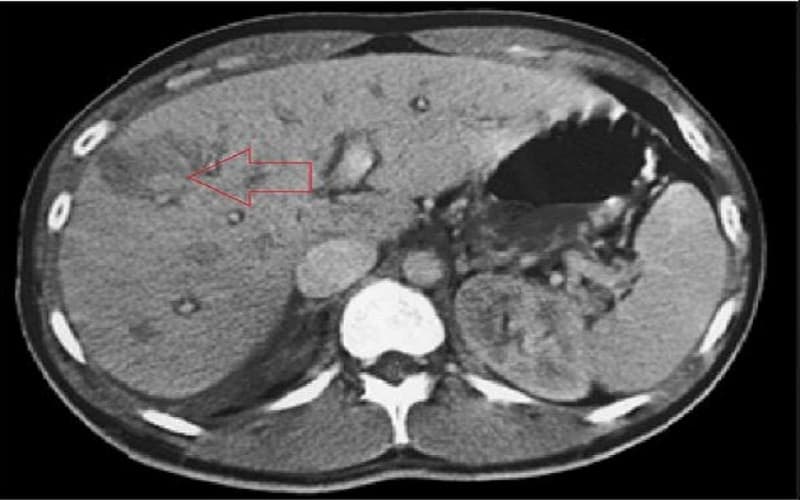

Chụp cắt lớp vi tính ổ bụng có thể được thực hiện trong những trường hợp cần thiết trong những trường hợp nghi ngờ về tắc nghẽn ống mật tụy chưa rõ nguyên nhân.

Minh họa tổn thương sán lá gan trên phim chụp cắt lớp vi tính